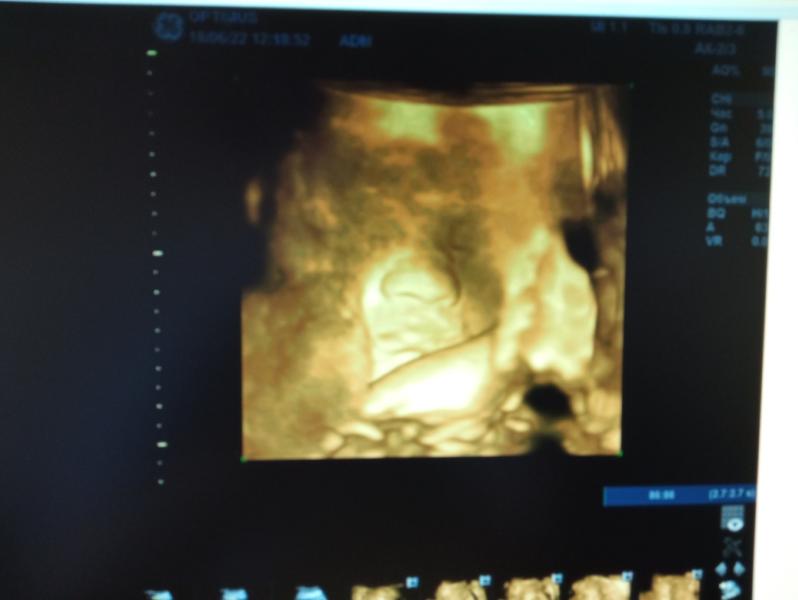

Вот и наш малыш, мальчик, скоро появится на свет, осталось совсем чуть-чуть 😇🙏не хотел чтоб на него смотрели, прятался ☺